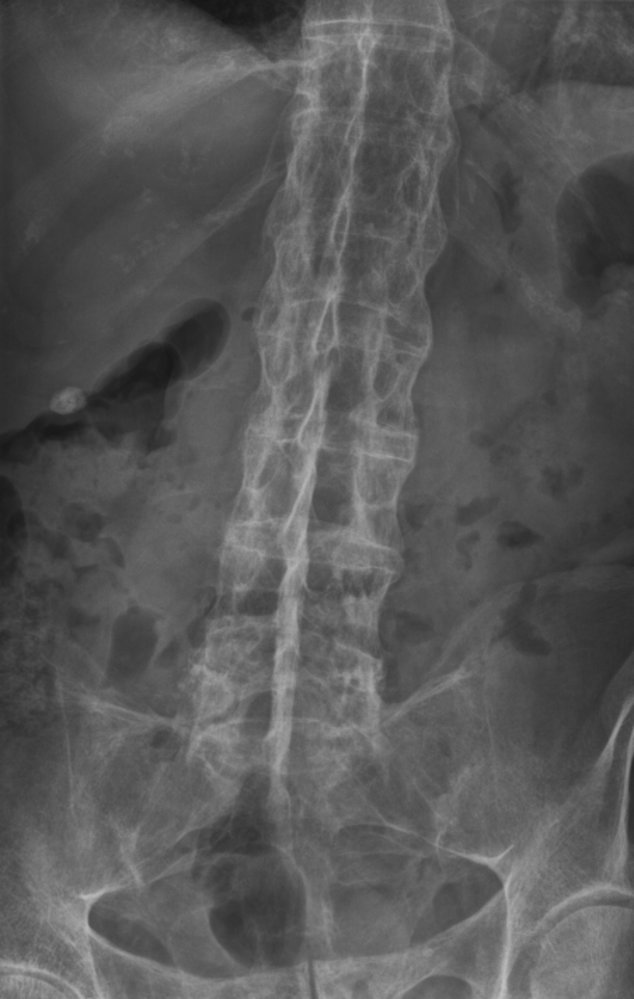

Spine (AP and lateral views)

• Characteristic findings

• Loss of lumbar lordosis: abnormal straightening of the spine

• Ankylosis of costosternal and costovertebral joints

• Dagger sign

• A radiodense line running through the center of vertebral bodies on AP view

• Caused by ossification of vertebral ligaments

• Bamboo spine: seen in later stages and is caused by the following

• Ossification of outer fibers of the annulus fibrosus resulting in ankylosis (fusion) of intervertebral joints

• Syndesmophytesbetween adjacent vertebral bodies (see “Syndesmophytes vs. osteophytes”)

• Shiny corners sign: reactive sclerosis of the superior and inferior margins of vertebrae